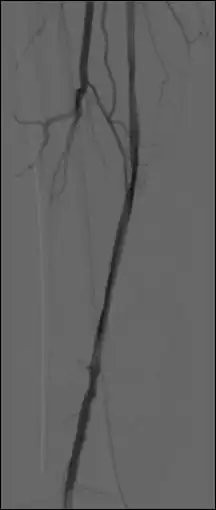

Use the Thick Slab module, in the MinIP mode to (effectively) integrate a number of live images so as to generate a vascular trace.

Pixel values displayed for subtracted images refer (incorrectly) to unsubtracted images – presumably because the subtracted image is generated in display memory only.

A plug-in is available from http://homepage.mac.com/kieranmaher/LogTransformplugin.zip (for purists) to take the Log Transform of an image sequence prior to running the subtraction process.